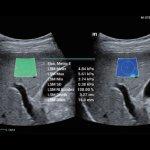

با توجه به اینکه دستگاه های جدید بررسی فیبروز کبد (سفتی کبد)بر پایه سونوگرافی میباشد،در مرکز تخصصی  فیرواسکن دکتر شماعی ،فیبرواسکن کبد صرفا توسط پزشک متخصص رادیولوژی  انجام می‌شود و علاوه بر انجام فیبرواسکن و ارزیابی فیبروز( سفتی ) کبد و تعیین میزان  کبد چرب، سونوگرافی کبد و بررسی کیسه صفرا و مجاری صفراوی نیز بدون دریافت هزینه انجام خواهد شد

مرکز تخصصی فیبرواسکن دکتر شماعی جز محدود مراکزی در مشهد میباشد که انجام فیبرو اسکن با استفاده از جدید ترین دستگاه ها انجام میگرد  و تمامی مراحل انجام فیبرواسکن و تجزیه و تحلیل اطلاعات و گزارش فیبرواسکن توسط پزشک متخصص صورت می‌گیرد.

با توجه به اینکه نتایج فیبرواسکن کبد نقش تعیین کننده در درمان کبد چرب دارد،لذا این مرکز متعهد به انجام فیبرواسکن کبد توسط پزشک متخصص و با صرف وقت لازم میباشد